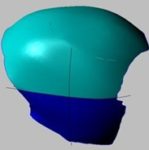

3D model

Protože poškození bylo velmi vážné, rozhodl se výrobce vyrobit protézu ze dvou částí.

Dr. P. Kasprzak vysvětluje – největší protéza zaznamenaná v literatuře měla 400 cm2. V našem případě – 280 cm2. Jedná se o druhý největší případ na světě (samozřejmě ze známých případů).